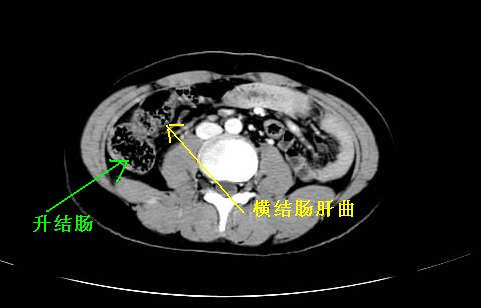

我坚决反对您的观点,该病例定位:横结肠肝曲与升结肠之间的肠系膜及部分肠壁。请看下图:

病灶巨大,少部分向肠腔内生长,大部分向长腔外生长。其密度不均匀,增强显示明显不均匀强化,并见有大片状始终不强化的不规则坏死液化区。虽然病灶中上部形态尚可,病人又如此年轻,但中下部形态、密度、强化特点强烈提示为恶性病灶。综上,我考虑本病例为:恶性胃肠道间质瘤。